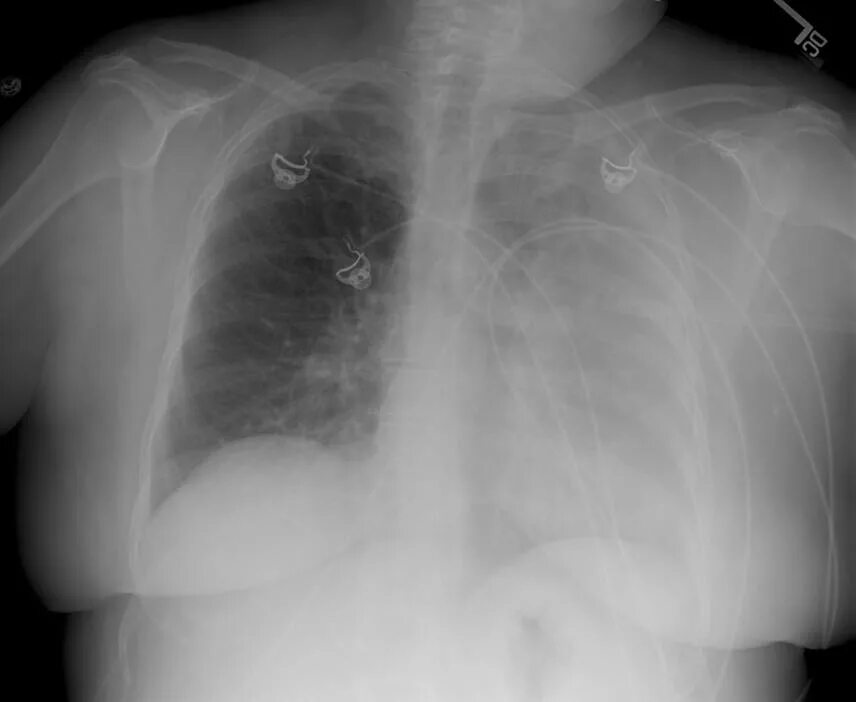

Normal abnormal